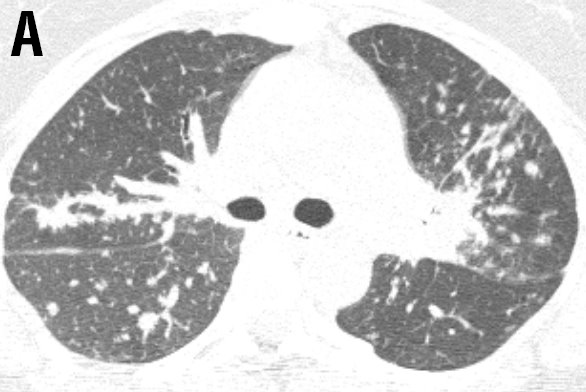

A 40-year-old female was referred to the ild care centre of the MUMC (a tertiary referral centre for sarcoidosis in the Netherlands) with refractory sarcoidosis. She was suffering from severe fatigue, shortness of breath on exertion, coughing, arthralgia and skin lesions, and also described exercise intolerance. She had no other medical history of note. An open lung biopsy showed non-caseating granulomatous inflammation consistent with the diagnosis sarcoidosis. Initially, she was treated with prednisone starting with 40mg daily. As this did not reveal a clinical improvement methotrexate was added (12.5mg once a week together with folic acid 5mg also once a week). However, this was without benefit, she deteriorated and responded neither to corticosteroids nor to methotrexate. At that time radiography and high resolution CT scan of the chest showed enlarged mediastinal en hilar lymph nodes and diffuse intrapulmonary lesions (figure 1 a and b).

Figure 1 Radiography and high resolution CT (HRCT) scan of the chest showed enlarged mediastinal and hilar lymph nodes (LN: 3) with intraparenchymal nodules (ND: 2), septal and non-septal lines (LS: 2) thickening and irregularity of the bronchovascular bundles (BVB: 1); parenchymal consolidations( PC: 3; including ground-glass opacifications) with focal pleural thickening (PL: 1), respectively (total visual Oberstein score (7,8) 13; Figure 1A).